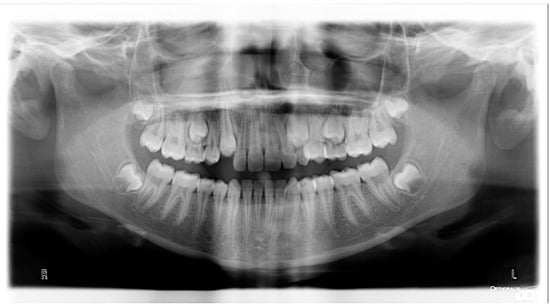

3.1. Clinical Case #1

3.2. Clinical Case #2

3.3. Clinical Case #3

3.4. Clinical Case #4